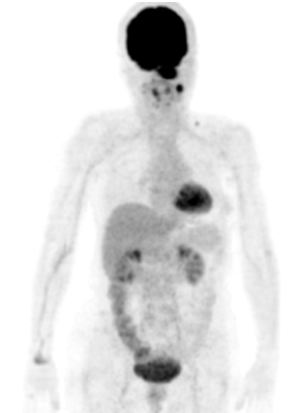

Chẩn đoán bệnh bao gồm: nội soi vòm mũi họng, sinh thiết u vòm, chọc tế bào hạch cổ, sinh thiết hạch, chụp CT, MRI vòm họng, xạ hình xương, ... và đặc biệt là chụp PET/CT (chỉ 1 lần chụp PET/CT toàn thân xác định được tổn thương vòm, hạch di căn và biết được di căn xa đến các cơ quan khác hay không, giúp đánh giá chính xác giai đoạn bệnh)

Mô phỏng tốt nhất trên PET/CT với hệ thống laser định vị 3 chiều. Vì PET/CT ghi hình dựa trên sự tập trung cao thuốc phóng xạ FDG vào các tế bào ung thư, cho hình ảnh chuyển hóa của khối u, sớm, chính xác hơn hình ảnh giải phẫu của CT đơn thuần (hình 1), xác định được mức độ xâm lấn của u cũng như phát hiện những di căn hạch kể cả với kích thước nhỏ ở mức độ phân tử, mức độ tế bào từ đó cho phép xác định thể tích xạ trị cũng như việc lập kế hoạch xạ trị được triệt để nhất (hình 2). Khi chụp mô phỏng: bệnh nhân trong tư thế nằm ngửa, cổ ưỡn sao cho đường thẳng giữa cằm - xương chũm vuông góc với mặt bàn; đầu bệnh nhân được giữ cố định bằng mặt nạ, tổng hợp từ loại chất dẻo đặc biệt.

Trên lâm sàng và CT không phát hiện được hạch cổ. Nên kế hoạch điều trị là: xạ trị đơn thuần, với tổng liều vào u vòm là 70 Gy, vào vùng cổ 2 bên 50 Gy.

Trên PET/CT phát hiện hạch di căn vùng cổ trái, nên đã thay đổi giai đoạn bệnh, và làm thay đổi kế hoạch điều trị: xạ trị kết hợp hóa chất, tổng liều vào u vòm: 70Gy, liều vào hạch vùng cổ trái: 70Gy, dự phòng vùng cổ phải: 50Gy.

Hình 2: Hình ảnh PET/CT phát hiện thêm được hạch cổ phải, CT bỏ sót không thấy

Do PET/CT có độ nhạy và độ đặc hiệu cao hơn nhiều so với CT (khoảng 30% hạch cổ di căn mà lâm sàng và CT bỏ sót), nên đã làm thay đổi giai đoạn bệnh và từ đó làm thay đổi thái độ điều trị cho người bệnh.